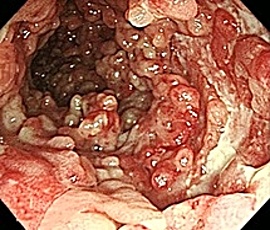

便潜血陽性にて精査目的に受診。腹部CT検査にて、脾弯曲部に限局した全層性炎症を疑う腸管壁の肥厚所見を認め、精査の結果、大腸クローン病と診断。内科的治療を継続したが、follow upの内視鏡所見で改善傾向がみられず、手術(腹腔鏡下結腸切除術)を施行。

内視鏡画像